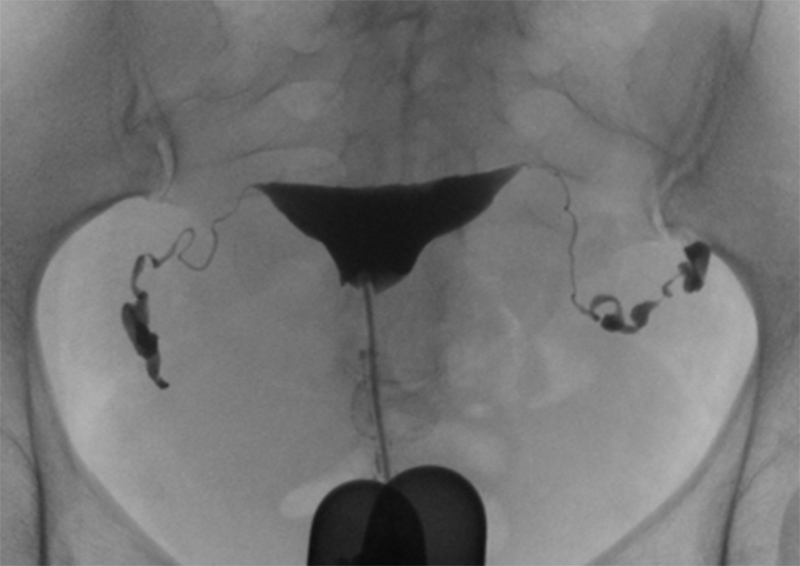

子宮卵管造影(HSG)

月経がほぼ終わっており、かつ排卵前の時期に行います。クラミジアと淋菌が陰性であることを確認した後に行います。月曜・水曜の13:30に来院していただき、すべて終わると16時ころになります。多少の痛みを伴います。検査後の仕事は予定しておかないことを勧めます。HSG検査後は妊娠しやすくなります。検査のみならず治療という意味もあります。